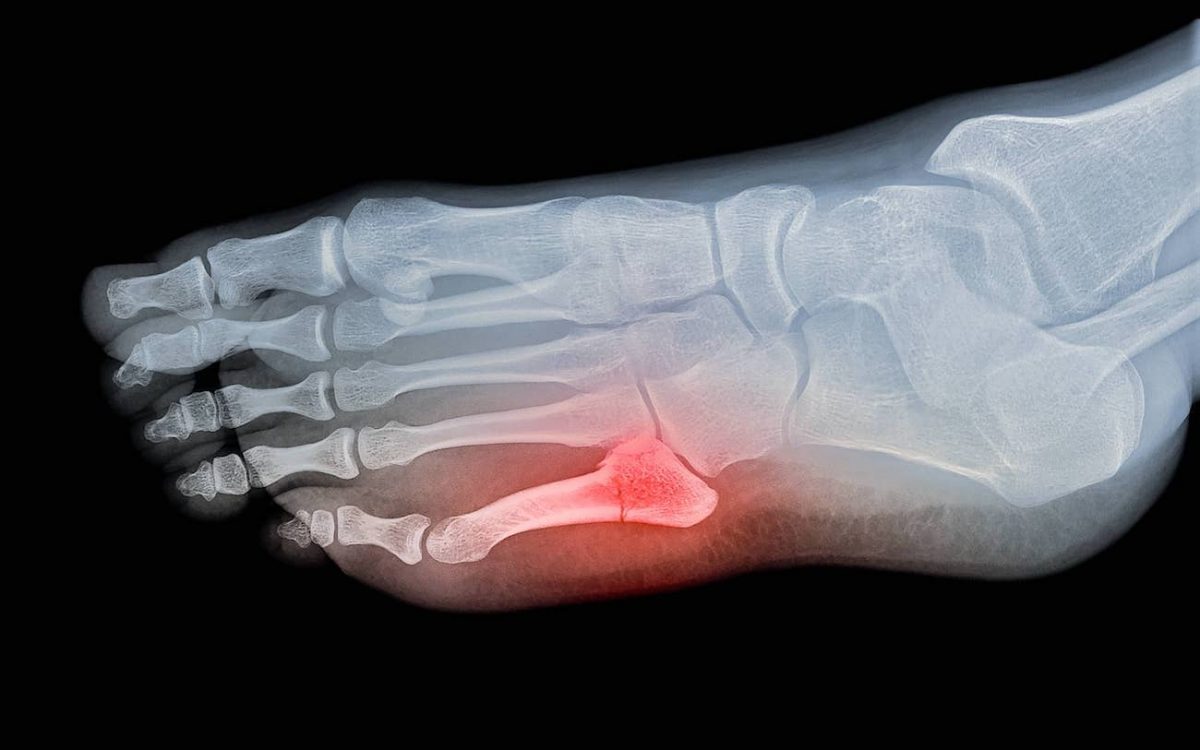

During my cross country season, I injured my toe—and honestly, I never expected something so small to have such a big impact. It wasn’t a major injury by any means, but it was enough to keep me from running. And for me, that was the worst part.